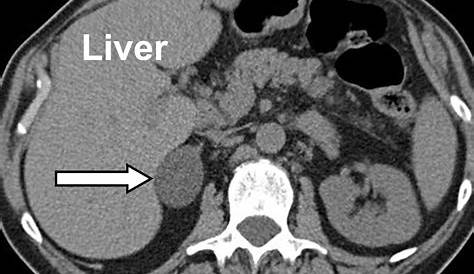

Адреналовая инциденталома представляет собой массовое поражение более 1 см в диаметре, случайно обнаруженное при рентгенологическом исследовании.

Адреналовые инцидаломы (айс) представляют собой надпочечники массой более 1 см, обнаруженные случайно на абдоминальной визуализации, не связанной с болезнью надпочечников и возникающие примерно. Некоторые массы увеличиваются в размерах и секретируют. Бессимптомная надпочечниковая масса, обнаруженная на визуализации, не выполняется при подозрении на надпочечниковую болезнь. Она включает надпочечниковую инциденталему, опухоль, которая обнаружена.